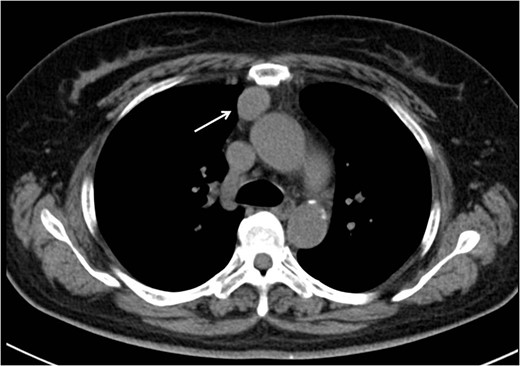

Follow-up CT performed 36 months after the operation revealed two pleural tumors located near the second and third ports (Fig. 2a and b). We suspected the pleural recurrence of thymoma and performed a second operation. Initially, the operation was performed only by VATS with three ports. After removing the severe adhesion between the lung and chest wall, we were able to identify the two tumors. As with the extrapleural tumor, the tumors arose from the intercostal space. Their surfaces were covered with parietal pleura with partial irregularity (Fig. 3). There were no other recurrent findings in the thoracic cavity. Given these findings, we diagnosed these tumors as port-site implantations after the first VATS.

Follow-up CT at 36 months after the operation revealed two pleural tumors locating at the second (a) and third (b) ports used in the VATS operation.